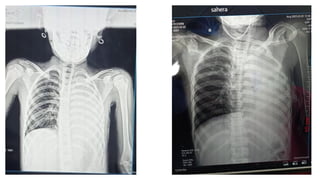

● USG thorax- left moderate pleural effusion.

● Left sided pleural effusion probably secondary to infective

etiology most likely bacterial

Final Diagnosis

Left sided parapneumonic pleural effusion with mild Anaemia with

severe thinness